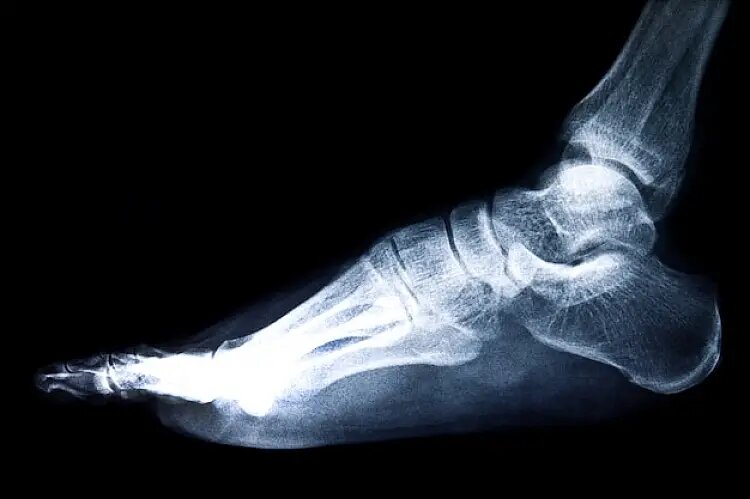

• Рентгенография. Это первый и наиболее распространенный метод диагностики переломов. Рентген позволяет увидеть состояние костей и выявить наличие переломов. Он также помогает определить тип и сложность перелома.